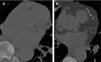

(A–C). Prevalent and pseudo-incidental screen-detected LC at baseline LDCT. Stage IA adenocarcinoma in a 60-year-old man from ITALUNG (A) appearing at baseline LDCT as a large (26mm in mean diameter) solid nodule in the right upper lobe (*). Pseudo-incidental stage IA squamous cell carcinoma in a 67-year-old man from ITALUNG (B and C) appearing at baseline LDCT (B) as an infra-threshold (5.2mm in mean diameter) solid nodule in the left anterior lobe (white empty arrowhead) and showing growth (10mm in mean diameter) at the first annual repeat (C).